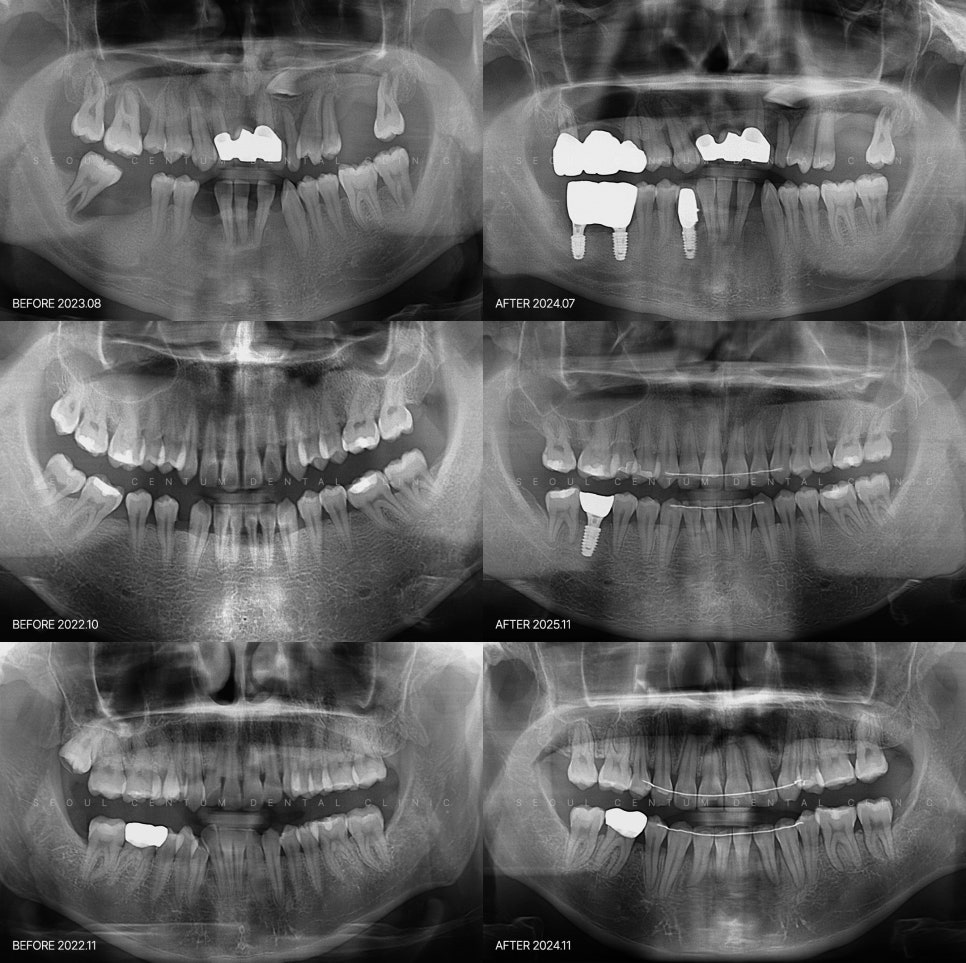

오래 지속되거나 치조골 손상이 심한 경우에는

발치 후 임플란트로 대체해야 할 수도 있습니다.

임플란트로 대체하는 방법을 고려해야 합니다.

보존 가능성이 낮다고 판단되면

임플란트를 하는 쪽으로 계획을 세우게 되고요.

고정이 제대로 되어야 하므로

뼈이식까지 함께해야 하죠.